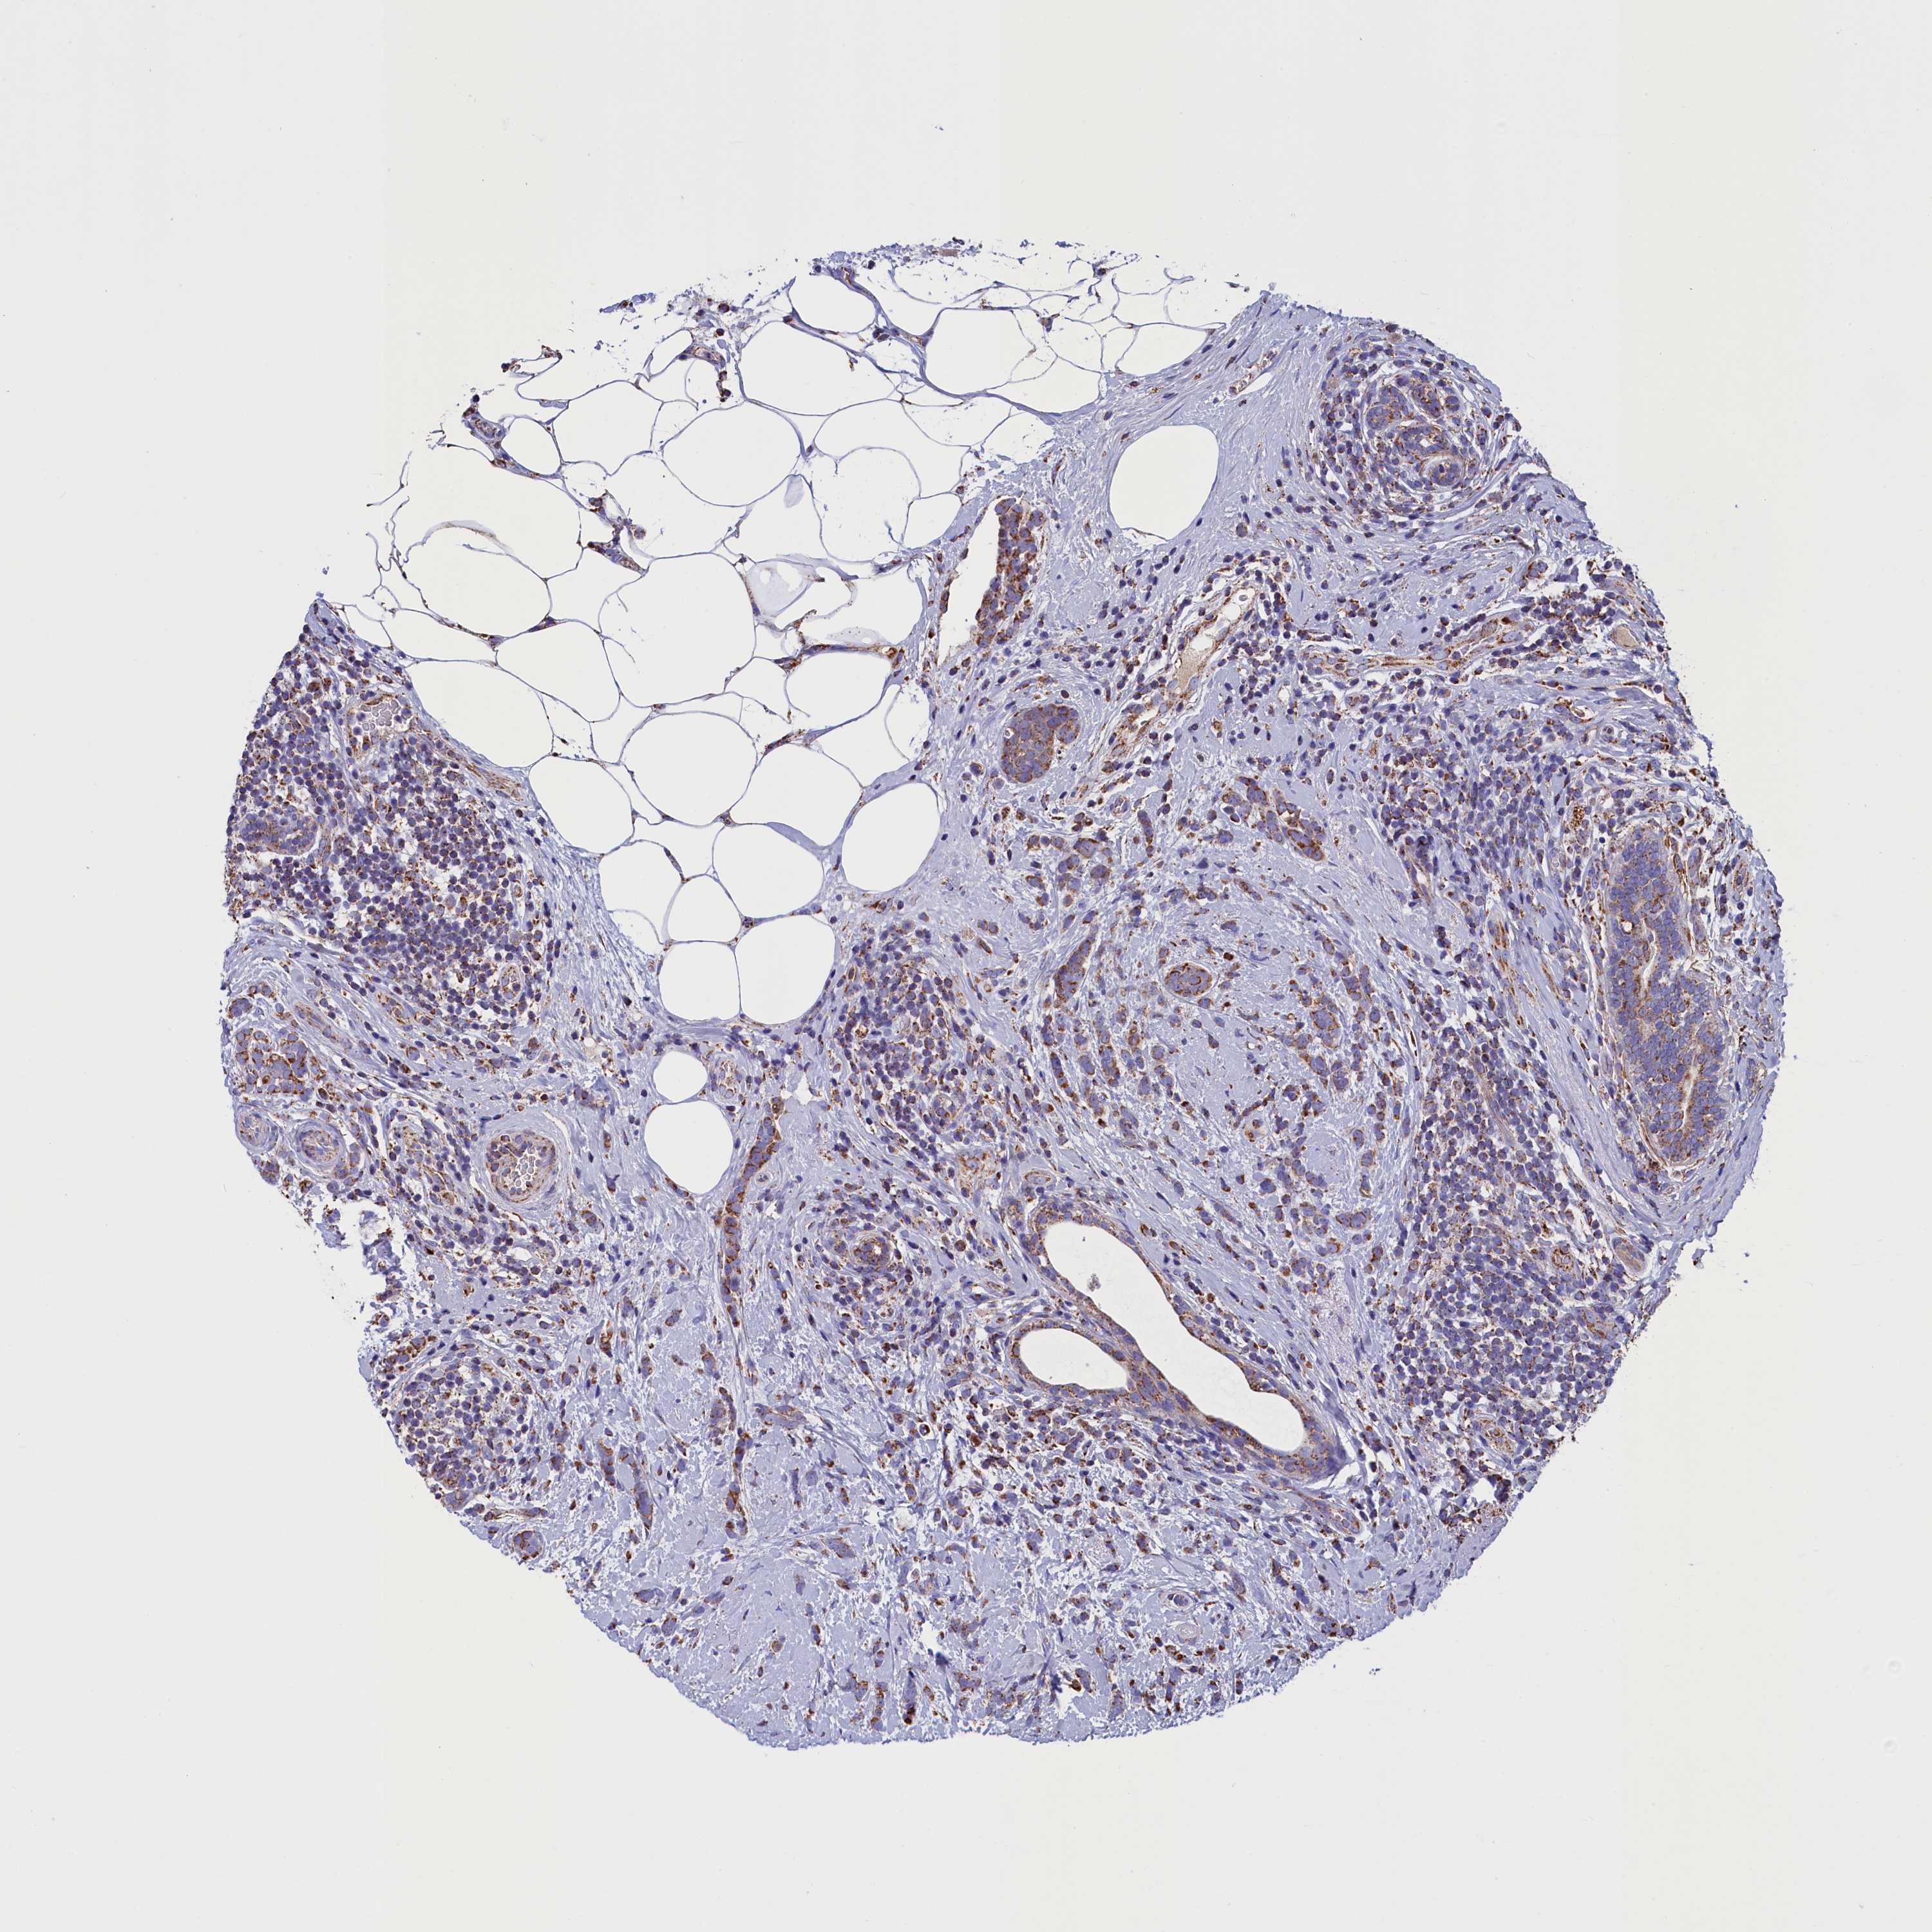

CANCER BREAST CANCER Show tissue menu

BRCA TCGA BRCA VALIDATION PROTEIN EXPRESSION